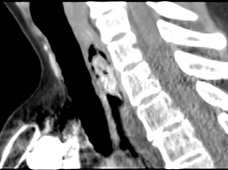

The pathological features were a multinodular proliferative lesion, composed of bland, uniform spindle-ovoid cells with no mitotic activity, in richly vascularized interstizial mixoid matrix with focal chronic inflammatory chances. The proliferative index (MIB1/Ki67) was 1%. Immunohistochemistry: neoplastic cells express smooth muscle actin. S100, H caldesmon, CD117, DOG1, CD34, SOX10, CKAE1-AE3 GFAP, MUC4, MDM2 were negative (Figures 2,3,4). Strikingly the histo-cytopathological analysis led to diagnosis of plexiform fibromyxoma.

Figure 3: Hematoxylin eosin staining